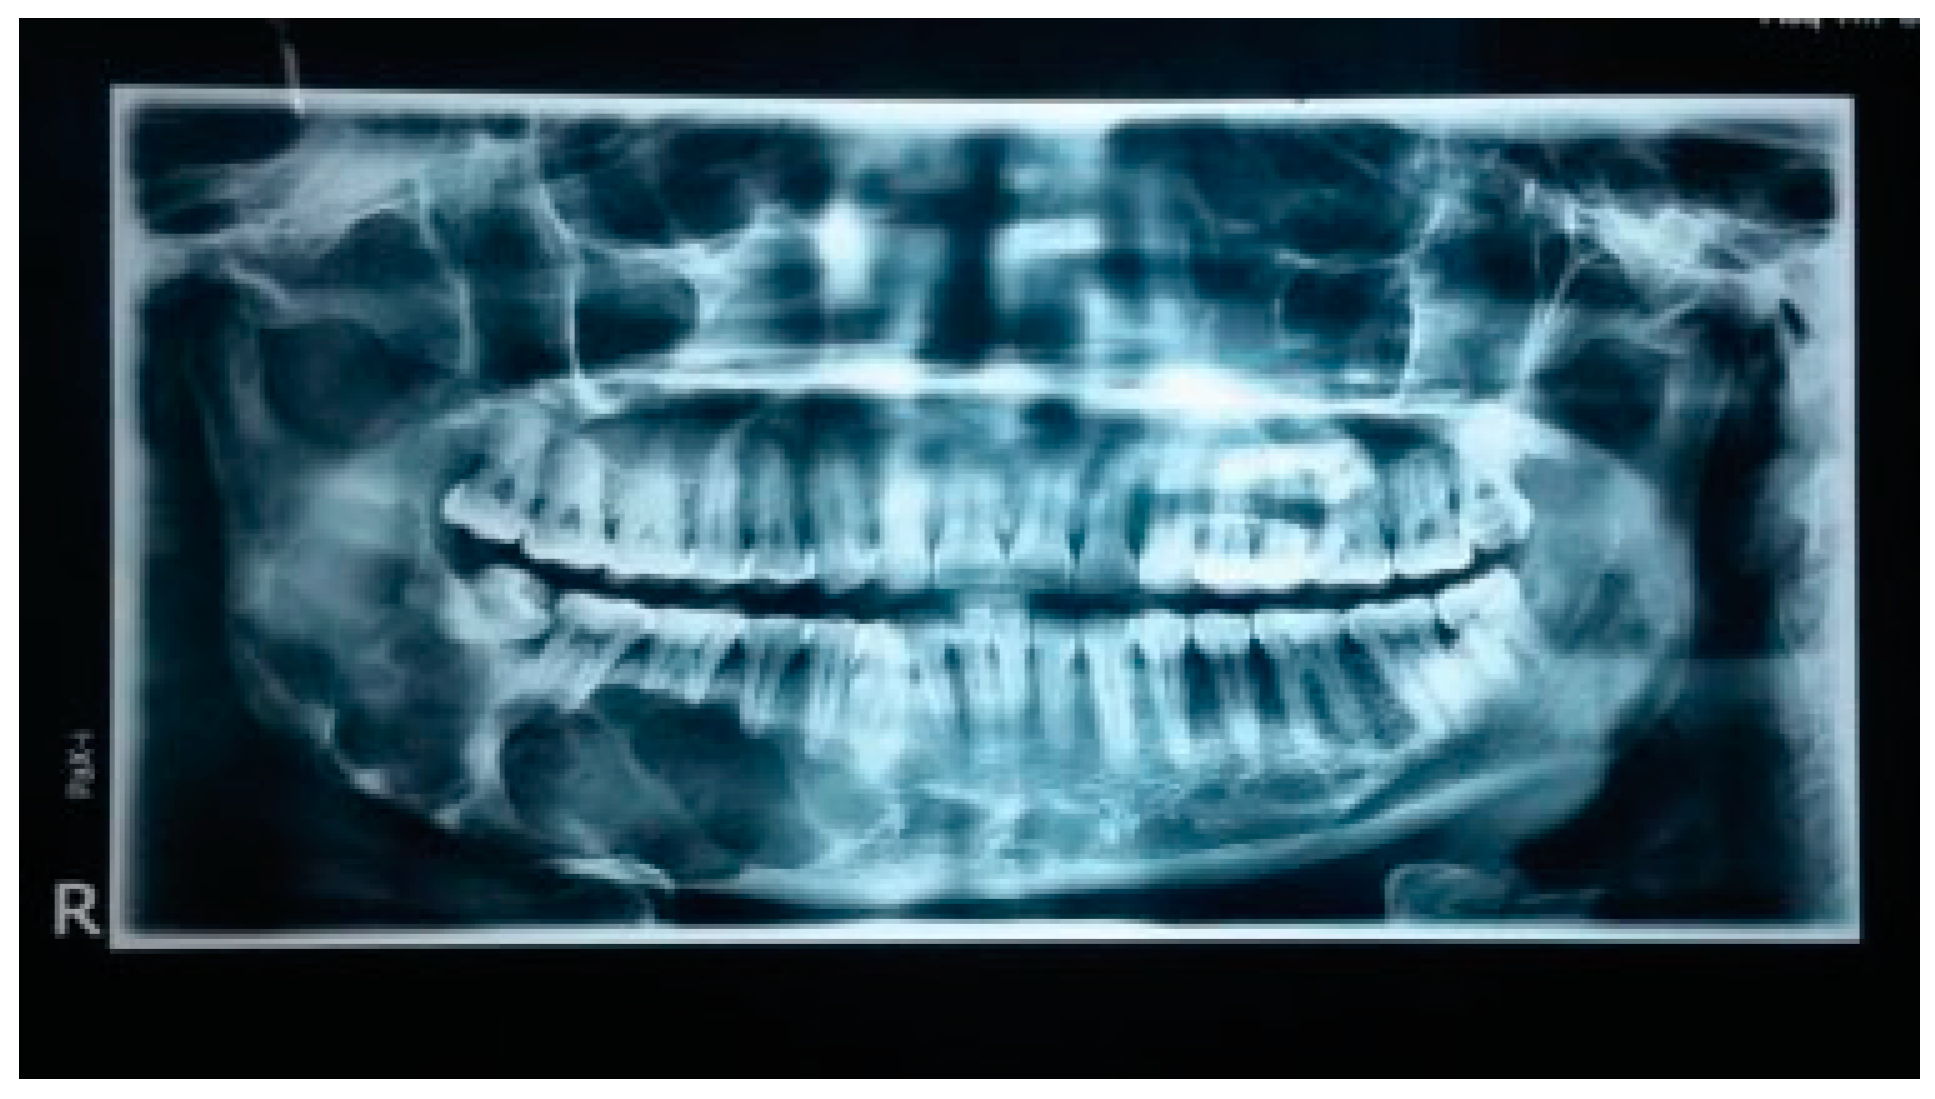

Clinical and radiological examination of the patient revealed large multilocular radiolucent lesion with well-defined border and involving the entire right side of the body and ramus of the mandible (Figure 3). Incisional biopsy of the lesion revealed a diagnosis of kerato cystic odontogenic tumor. Following definitive diagnosis, segmental resection from the canine region with disarticulation (TORD) of the ipsilateral condyle and immediate reconstruction were planned as a definitive treatment for the patient.

Figure 3. Orthopantomogram showing a large multilocular radiolucent lesion with well-defined border and involving the entire right side of the body and ramus of the mandible.